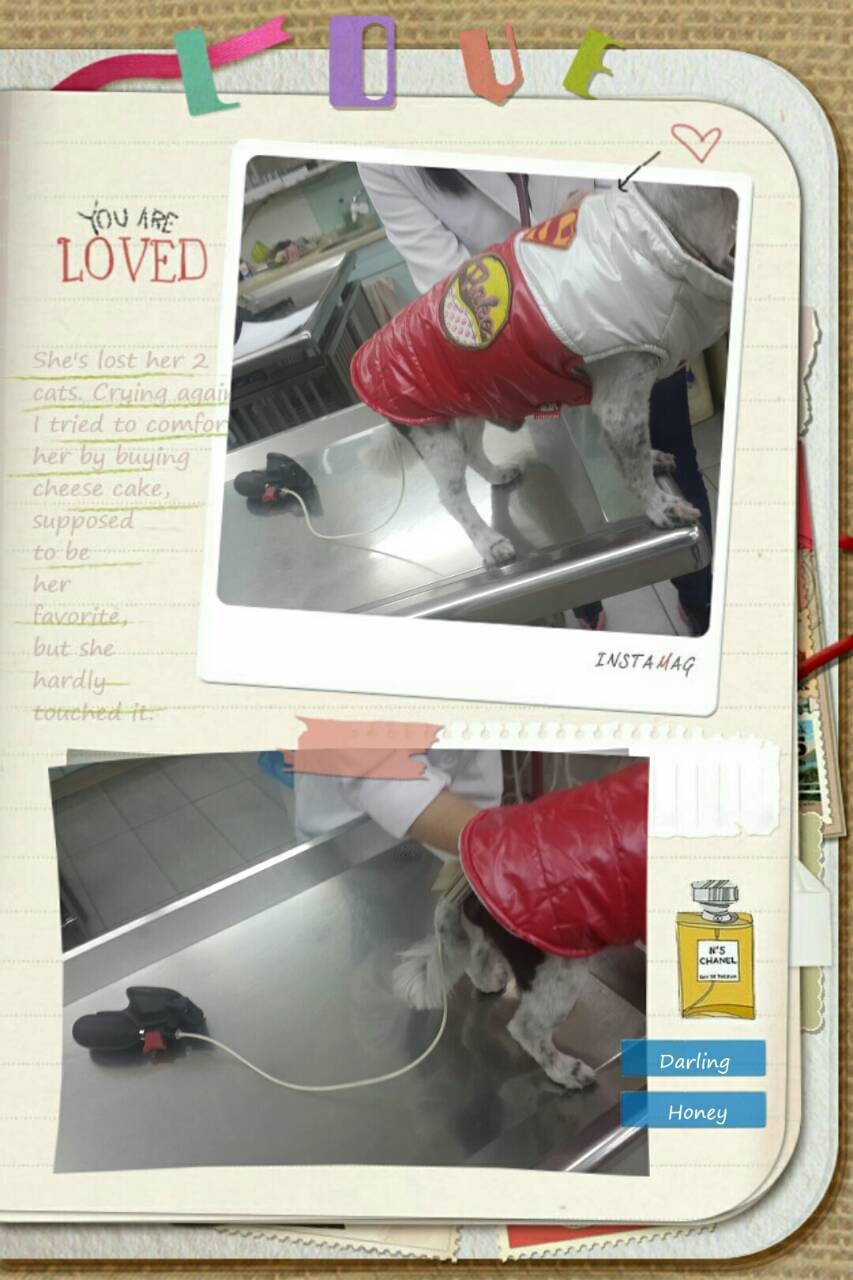

▼原來狗狗的量血壓計長這樣…..不過要反覆個三次才能確定血壓…

經過動物醫生細心的看診和檢查(量血壓、聽診)後

好消息是:咳嗽的情形已經改善,可是醫生檢查後發現血壓還沒有穩定下來…

所以我們要回家繼續用藥治療,希望下次(兩個星期後)回診血壓可改善,不然就要調藥了~